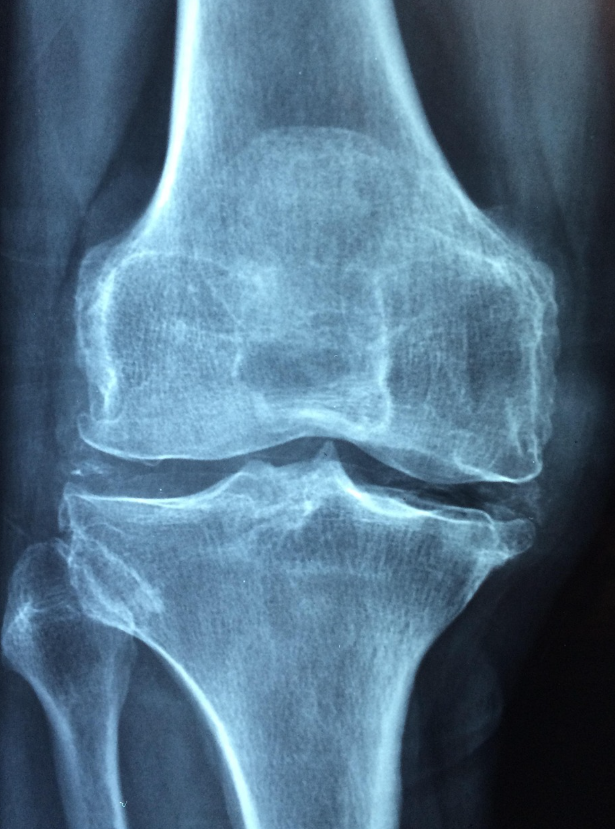

진단은 X선 검사에서 관절 간격의 감소와 골극 형성을 확인하며, 필요시 MRI를 통해 연골과 활액막 상태를 평가합니다. 치료는 진통제, NSAIDs, 히알루론산 주사, 온찜질과 물리치료, 체중 조절, 저 충격 운동, 필요시 인공관절 수술까지 진행될 수 있습니다.